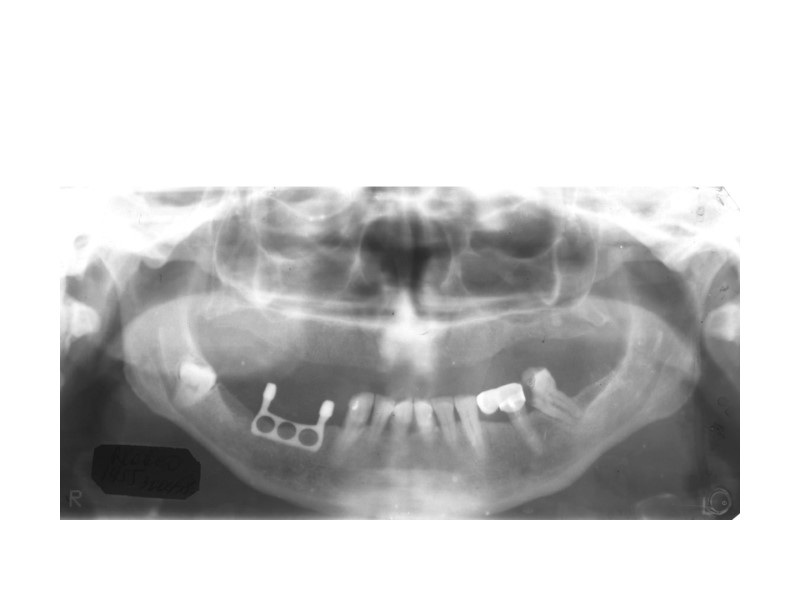

Перелом правой ветви нижней челюсти – поперечная линия перелома в ментальной области, после репозиции и фиксации.